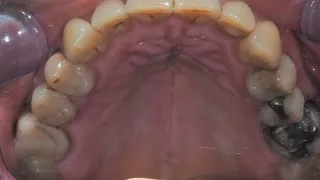

2a. 2b. Initial intraoral view of the molar.

2a

2b

5. Occlusal view after atraumatic tooth extraction.

5

8. Occlusal view of the composite socket sealing with a 3mm provisional titanium retained SSA as fabricated by Gary Finelle.

8

9. Intra oral view with the SSA in place.

9